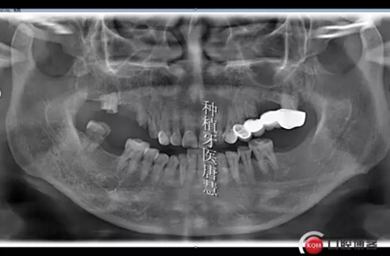

患者劉xx,女,55歲,右上后牙區(qū)殘根,來診咨詢種植。

查見14、15、17殘根狀,松動II°,叩診不適,根尖區(qū)有大面積陰影;16、47缺失,48大面積齲壞

治療計劃:拔除14、15、17、48,種植14、16、17、固定修復(fù),47種植修復(fù),患者要求先種植14、16兩顆